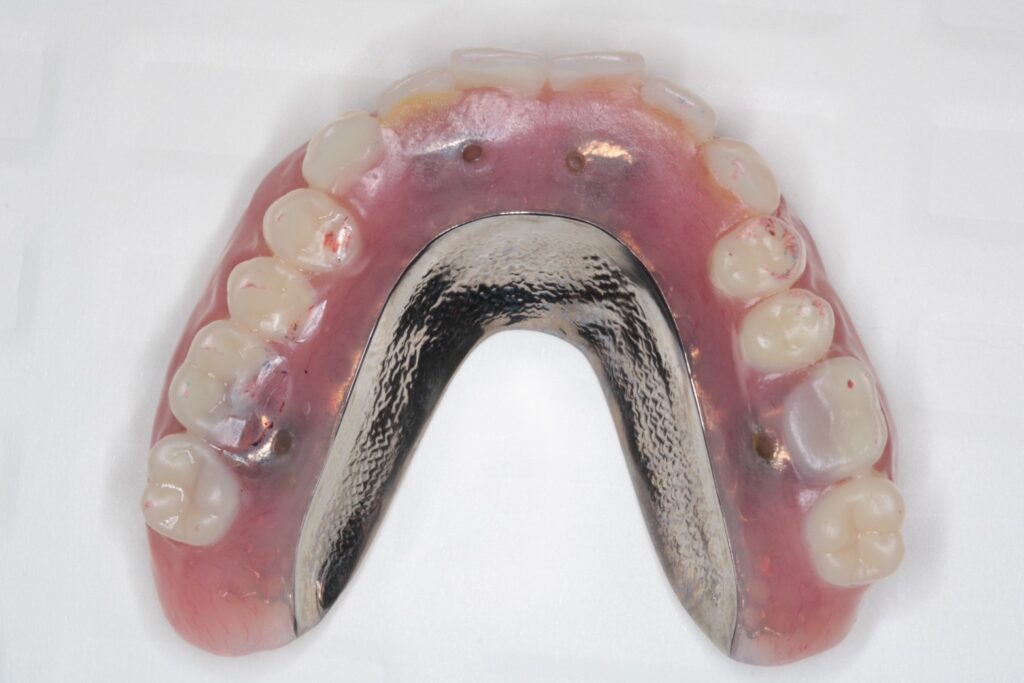

今回使用したのは、精密性が高いコーヌステンチャー(ロケーター義歯よりも精密)。

【コーヌスデンチャー】

今回採用した「コーヌステンチャー」は、

■フィット感が非常に高い

■安定性に優れている

という点が大きなメリットです。

ロケーター義歯のように着脱のしやすさを重視したタイプもありますが、

精密な噛み合わせや長期の安定性を求める場合には、コーヌスが適している ケースも多くあります。

どちらを選ぶべきかは、患者さまのお口の状態や生活スタイルに合わせて最適なものをご提案しています。